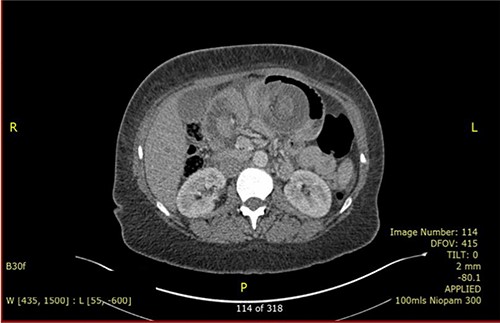

A 37-year-old lady presented with 1-day history of sudden onset of severe generalized abdominal pain that was associated with multiple episodes of vomiting. She had occasional similar episodes before, but those were usually milder and were self-resolved. Her past surgical history includes RGYBP surgery 23 years ago and six caesarean sections. She had lost 11 stones of weight in 1 year after the gastric bypass surgery. On physical examination, her abdomen was distended and diffusely tender. Her blood investigation showed low Hb (85 g/dl), raised C-reactive protein (146) and normal white cell count. She had computed tomography (CT) scan (Fig. 1) which concluded intussusception of small bowel with an area of intramural gas highly suspicious of bowel ischaemia. Diagnostic laparoscopy was decided.

CT scan is the preferred imaging modality for early identification of intussusception [9]. Characteristic findings are target signs and multiple concentric rings as seen in this case. While CT can diagnose intussusception, there is limitation in identifying its underlying aetiology. Other imaging modalities, such as plain abdominal films or ultrasonography, can be used but is less practical in diagnostic purpose compared to CT scan.